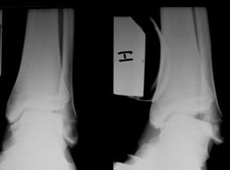

Es la falta de estabilidad en el tobillo. Esta lesión altera el funcionamiento normal del tobillo y puede producir sensación de debilidad en el tobillo. Si además hay dolor, hay que descartar otras lesiones asociadas.

La inestabilidad de tobillo aparece cuando se rompen los ligamentos que estabilizan el tobillo. Los ligamentos que estabilizan el tobillo son: ligamento lateral externo, ligamento lateral interno y sindesmosis. El ligamento cicatriza correctamente si no hay incongruencia articular. El tratamiento conservador se aconseja en las lesiones agudas si el estudio radiológico muestra congruencia articular del tobillo.